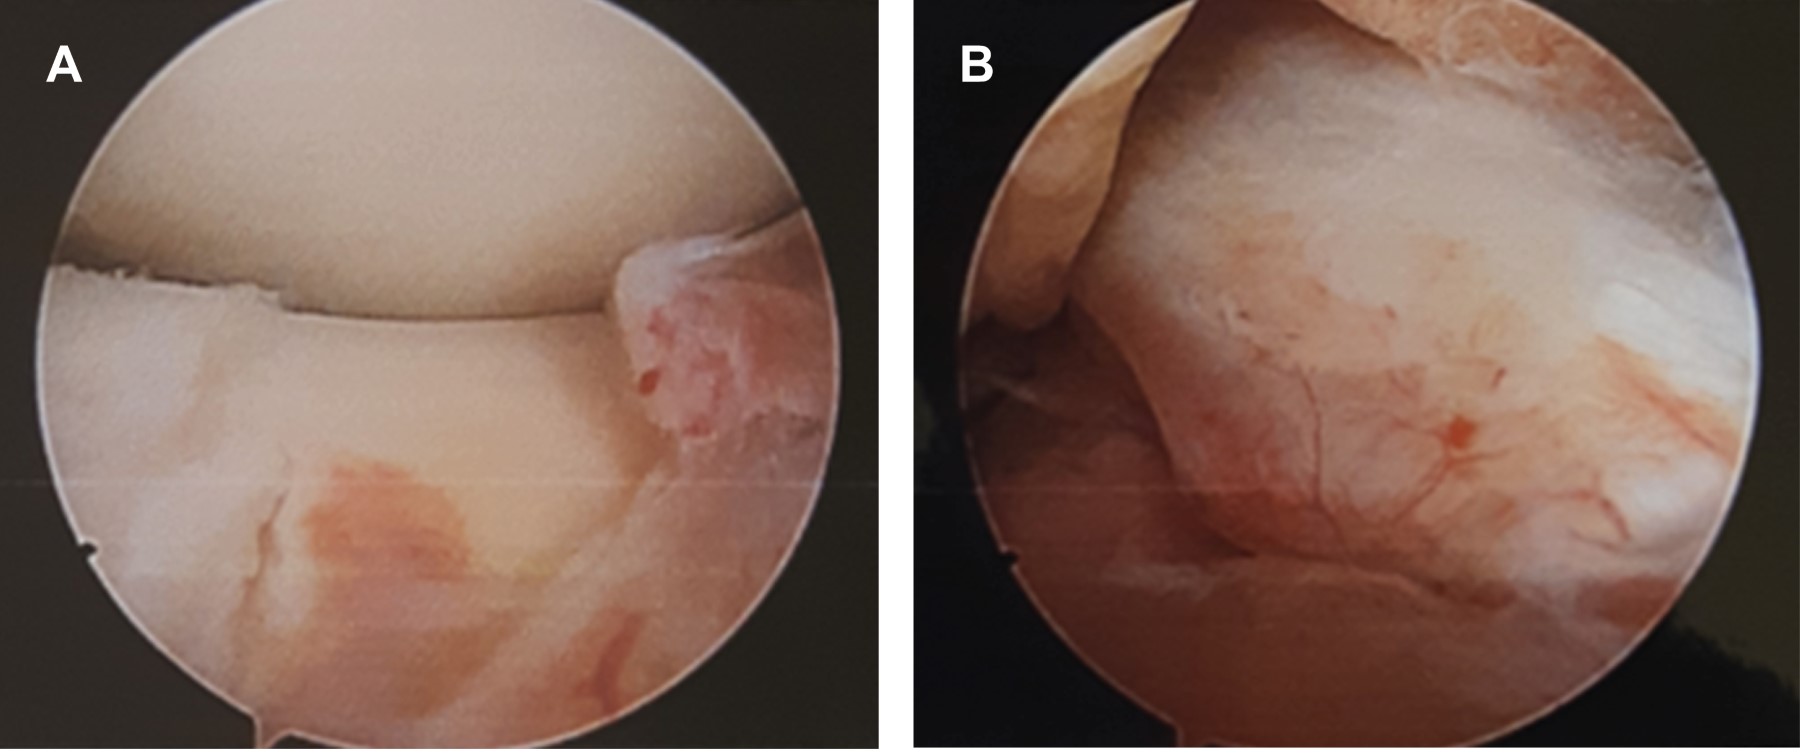

Paciente masculino de 11 años que acude a valoración tras presentar caída mientras jugaba en un brincolín, con lo que desarrolla dolor y aumento de volumen de rodilla derecha así como equimosis leve y limitación para el apoyo con la extremidad. Se realizan estudios de imagen (Figuras 1 y 2), entre ellos radiografía de ambas rodillas en la que se describe irregularidad de la meseta tibial de rodilla derecha, compatible con avulsión de la espina tibial. La tomografía computarizada mostró fractura de meseta tibial en topografía de inserción de ligamento cruzado anterior. La resonancia magnética reporta fractura por avulsión de la apófisis espinosa anterior de la tibia, y zonas de contusión ósea con lesión osteocondral grado 1-2 de cóndilo femoral lateral y plataforma tibial, además de meniscopatía intrasustancia medial grado 2.

Se programó para reducción de meseta tibial por vía artroscópica mediante sistema TightRope, para lo que se coloca al paciente en decúbito supino, con rodilla a 90o de flexión y sujetador, se realizan portales anteromedial y anterolateral de rodilla derecha, con lo que se vacía hemartrosis de rodilla derecha, limpiando el foco de fractura. Se procede a realizar incisión en tibia proximal en superficie anteromedial para perforar túnel tibial mediante colocación de guía para ligamento cruzado anterior a 55o, se perfora con broca 3.5 mm a través de fragmento de espina tibial reducido con la misma guía, introduciendo desde túnel tibial un FiberStick con sutura de FiberWire para recuperar suturas de TightRope. Se extraen cabos de sutura a través de túnel tibial y se pasa TightRope a través de portal anteromedial, con las suturas atravesando fragmento de espina tibial. Se gira TightRope a su posición horizontal y se tensa con cuidado de no dañar el fragmento de espina tibial (Figuras 3 y 4), se fija en pared anteromedial de tibia proximal con otro TightRope distal circular anudando suturas, y se cortan excesos de éstas. Se cierran portales e incisión de tibia proximal, se cubre con vendaje de Jones y se coloca rodillera mecánica graduada a 0° de extensión. En consultas subsecuentes se fue ampliando el arco de movilidad de rodilla a 45° de flexión y se verificó con control radiográfico la consolidación del foco de fractura. Comienza con apoyo parcial y continúa con fisioterapia en casa cuatro semanas después de la cirugía, ampliando el arco de movimiento a 90o de flexión.

Figura 2